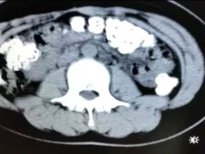

Kabızlık şikayetiyle Doğu Çin'in Zhejiang Eyaletindeki Zhuji Halk Hastanesi'ne kaldırılan Xiao Shen'in midesinden 100 'Tapioca' denilen jelibon toplarının yapıştığı saptandı. Jelibon toplarının mideye yapışma sebebi ise doktorları bile şoke etti.

Çin'de 14 yaşındaki Xiao Shen, 4 gün boyunca kabızlık çekince hastaneye kaldırıldı. Midesinden öyle bir şey çıktı ki doktorlar bile şoke oldu.